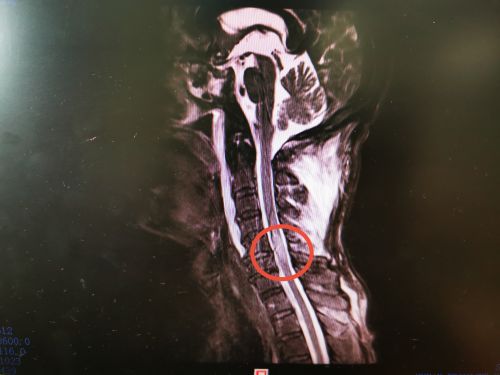

李爷爷术前磁共振显示:颈5-6水平脊髓挫伤。

湘潭70岁的李爷爷摘杨梅时从5米高的树上摔下,头部着地昏迷,约一小时才醒来,全身多处疼痛,头部更是剧痛难忍,还伴有双上肢麻木、乏力,双下肢不能活动,转送至省人民医院脊柱外科,被诊断为“颈椎骨折并脊髓损伤”,因其高位截瘫并头部蛛网膜下腔出血,随时都有生命危险。待病情平稳后,由沈雄杰主任医师和常磊主治医师在全麻下为其施行颈椎后路减压复位植骨融合内固定术。患者术后双下肢肌力由术前的0级恢复到2级。